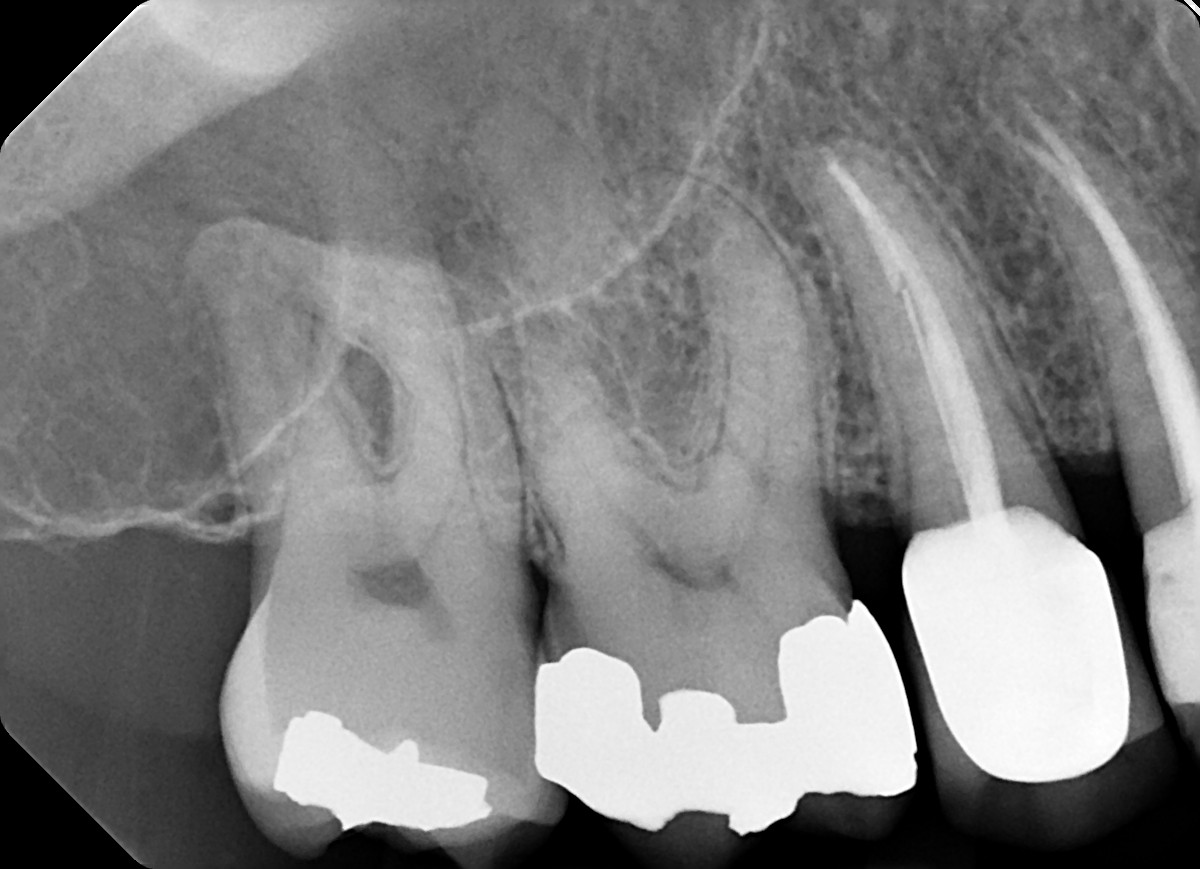

9. What condition can be selected or the root canal treatment of tooth # 1.1?.

10. What condition can be selected or the root canal treatment of tooth # 3.6?

11. What option can be selected for root canal treatment of the tooth #3.6?

12. What option can be selected for root canal treatment of the tooth #3.7?